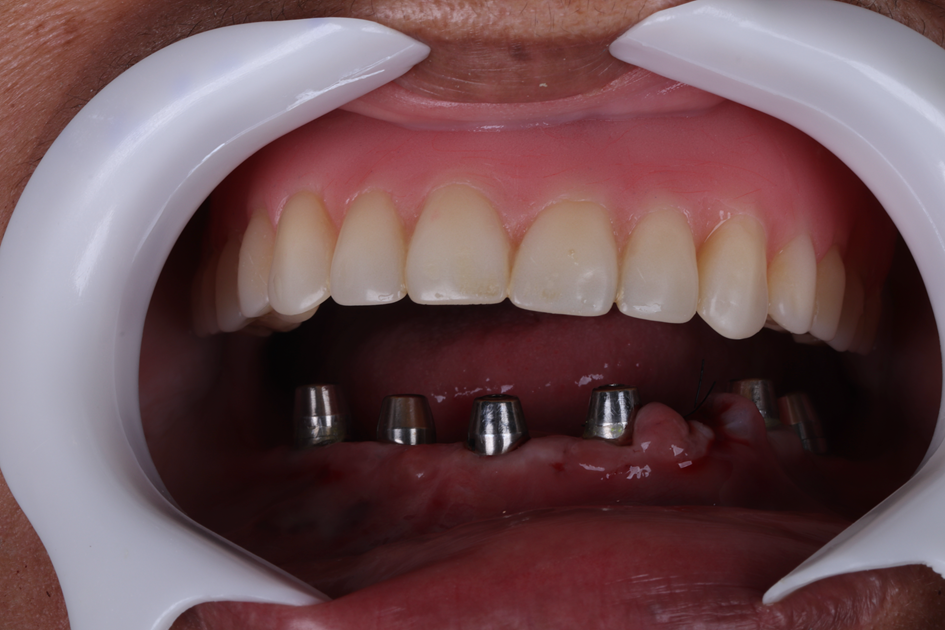

Logo após a instalação dos implantes foram posicionados mini-pilares cônicos em cada implante. Após 28 dias, os mini-pilares cônicos foram torqueados com 30N, e realizou-se a moldagem para confecção da prótese definitiva, em resina, respeitando o protocolo de carga precoce.

Optou-se por confeccionar a prótese em um intervalo de quatro dias, respeitando etapas essenciais para garantir adaptação e estética adequadas. Foi realizada a prova dos dentes em cera, seguida da prova dos dentes montados sobre a barra metálica, e, por fim, a instalação da prótese definitiva.

Figura 26 – Foto da prótese protocolo inferior definitiva instalada em boca.